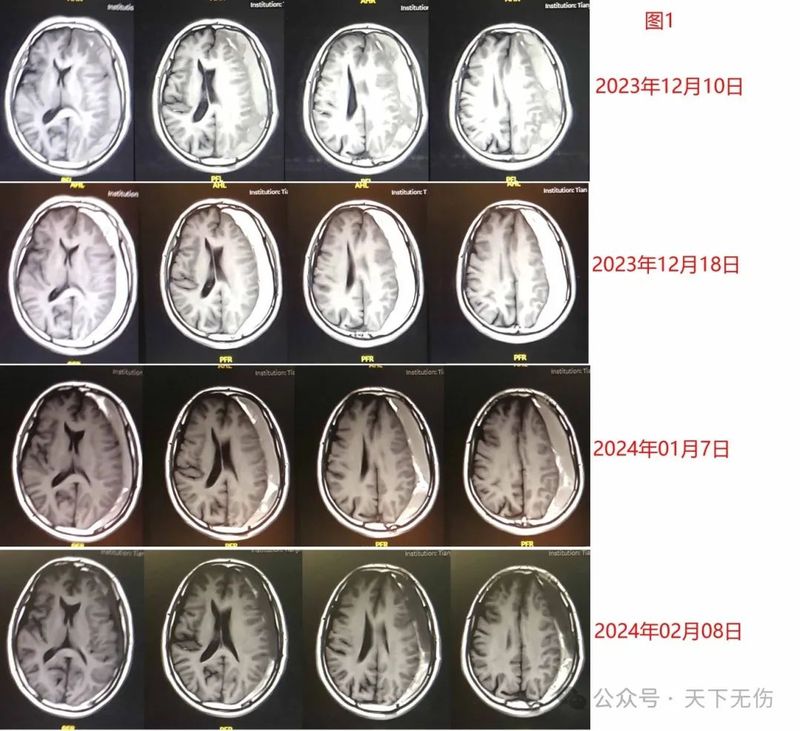

我治療的慢性硬膜下血腫患者越多,遇到的“怪”事就越多。同樣是慢性硬膜下血腫,有人恢復奇快,有人恢復很慢。為什么同病不同命呢?是個體差異?還是其他原因?患者Z大娘Z大娘,今年70歲。她是4月21日因為左側肢體乏力被家人送到我院急診,確診為右側硬膜下血腫。老人家患骨髓增生異常綜合征10余年,長期貧血、肝功能異常,此次發(fā)病后臉色蠟黃,急診醫(yī)生推薦她找我診療。4月22日我在門診看到她時,她已經無法獨立行走。緊急收入院,家屬傾向于藥物治療。我們請相關內科同道會診確定她可以使用他汀和激素,然后實施了他汀加激素治療。僅僅3天,她精神狀態(tài)大為好轉,1周后復查,顯示血腫已經減少,囑她出院后注意事項后,老人被家人滿是期許地接走。5月16日距離她出院接近3周,老人家走來我門診隨訪,復查CT顯示血腫已經幾乎完全吸收(圖1),只是化驗顯示轉氨酶有點異常。我驚訝于她的快速恢復,囑咐她停掉他汀和激素,補充了保肝藥,老人一家興高采烈地回家了。圖1患者P女士P女士,56歲,確診白血病后在血研所化療,導致血小板僅1000/ml。由于她自己和家人都知道血液異常,因此平時特別小心,幾乎總是臥床不動,不太有機會受傷。她突然頭痛劇烈,很快確診慢性硬膜下血腫,推測是長期便秘導致的腹壓變化和顱壓變化引起的硬膜下出血。她的主治醫(yī)師是我朋友,參照我的治療方案給患者他汀治療,但4天后復查CT顯示血腫增大。這位醫(yī)生咨詢我,我擔心她是白血病腦病,但還是推薦他試試加上地塞米松治療,如果是真血腫,應該會有效。約1周后,她的癥狀明顯緩解,復查頭CT顯示血腫幾乎消失,我慶幸她不是得了白血病腦病。然后我就失去了她的消息。5月13日她和她年輕的兒子來門診咨詢她剛剛發(fā)生的蛛網(wǎng)膜下腔出血是否嚴重。我了解到此次少量蛛網(wǎng)膜下腔出血發(fā)生時機也似乎跟便秘相關,所幸復查CT顯示蛛網(wǎng)膜下腔出血已明顯消散,同時也證實我的治療導致了硬膜下血腫完全吸收(圖2)。我教她食療改變便秘,母子倆非常寬慰地離開了門診。圖2患者F大爺顯示神奇效果的還有F大爺,93歲,身體硬朗。他去年11月不小心輕微摔傷,1個月后右下肢乏力,查出慢性硬膜下血腫。患者堅決拒絕手術,我收他住院接受藥物治療加頭頸淋巴按摩,顯示有效。1周后出院,繼續(xù)他汀加激素治療,患者右側肢體乏力在好轉,但似乎療效緩慢。5月9日再次就診我門診,頭CT檢查顯示他的血腫已經幾乎治愈(圖3)。陪他來的是他的3個六七十歲的兒子,聽到好消息后,高興得手舞足蹈,連聲感謝我,匆匆陪著老人回家了。圖3患者L先生盡管多數(shù)患者治愈,但也確實遇到難治的患者。L先生,52歲,輕微外傷后頭痛,復查頭CT發(fā)現(xiàn)右側硬膜下血腫。患者沒有經過規(guī)范治療,反而跑去拔罐子,結果左側肢體開始行走乏力,復查顯示血腫增加了數(shù)倍,慌慌張張從吉林跑到我門診來尋求藥物治療。3月18日我收他住院,經過1周治療血腫有所減少。叮囑他要遵守注意事項,他答應得很好,而且接近一個月就復查一次影像匯報給我,他的血腫也在繼續(xù)減少。5月8日他突然聯(lián)系我,說這次復查顯示有新鮮出血,很著急。他的影像確實像是有了新鮮出血。我跟他聯(lián)系,希望他就近手術治療。結果他再次來我院住院治療。我為他追加短期的他汀加激素治療,1周后顯示他的血腫又開始吸收(圖4)。我后來才知道,他回家后沒有嚴格遵守我擬的注意事項,有用力過度和鍛煉過度,還搬了重物……問他是否愿意手術,他苦笑說,這次知道不遵守注意事項的厲害了,希望再次藥物治療,以觀后效。我相信他如果嚴格遵守注意事項,一定會很快好轉。圖4思考我在思索為什么得了血液系統(tǒng)疾病的兩位女士和那位超老年先生恢復得這么快,而這位中年男性恢復得不夠理想。我想可能是免疫機制在發(fā)揮作用。那2位血液病患者顯然因疾病本身和化療都有嚴重的免疫缺陷,而慢性硬膜下血腫是一種炎性疾病,如果患者已經有了全身的免疫抑制,可能反而難以在血腫腔內形成劇烈的炎性反應,反而有利于血腫吸收?而這位超老年長壽明星,本身就有超老年的資本,聲音洪亮,中氣十足,他可能有恰到好處的免疫力。那位受了波折的中年男士,正值壯年,是外傷導致血腫,本身有較為健全的免疫力,也因此,第一輪治療顯示他的血腫快速縮??;此次他的血腫再次增大與他用力過度導致再出血有關。看來免疫力在這里發(fā)揮了關鍵作用。弱的免疫力,對硬膜下血腫不是什么壞事?似乎上帝關上一扇窗的同時,為患者打開了另一扇窗?但是好的免疫力也應該可以促進血腫吸收?激素和他汀似乎對于一些特殊的患者、在特定的時間能發(fā)揮恰到好處的免疫調節(jié)作用,促進血腫吸收。這些患者還都接受了頭頸淋巴按摩,是否這也調節(jié)了免疫呢?我不知道,我們后續(xù)將進一步去爭取經費、深入研究。專家介紹江榮才教授二級教授,主任醫(yī)師,博導,海河醫(yī)學學者天津醫(yī)科大學總醫(yī)院神經外科中心常務副主任,科副主任,NICU主任天津市131第一層次人才,天津市醫(yī)學會神經重癥分會首任主任委員,天津市醫(yī)學會神經外科副主任委員中華醫(yī)學會神經外科學分會委員、腦外傷學組副組長中國醫(yī)師協(xié)會神經外科醫(yī)師協(xié)會神經重癥專委會副主任委員國家創(chuàng)傷醫(yī)學中心顱腦創(chuàng)傷專業(yè)委員會副主任委員中國老年保健協(xié)會神經外科學創(chuàng)新與轉化分會首任會長擅長復雜重型腦外傷、腦出血及慢性硬膜下血腫的診療。是他汀治療硬膜下血腫的主要發(fā)明者,治療慢性硬膜下血腫患者超1000名,總治愈率約90%